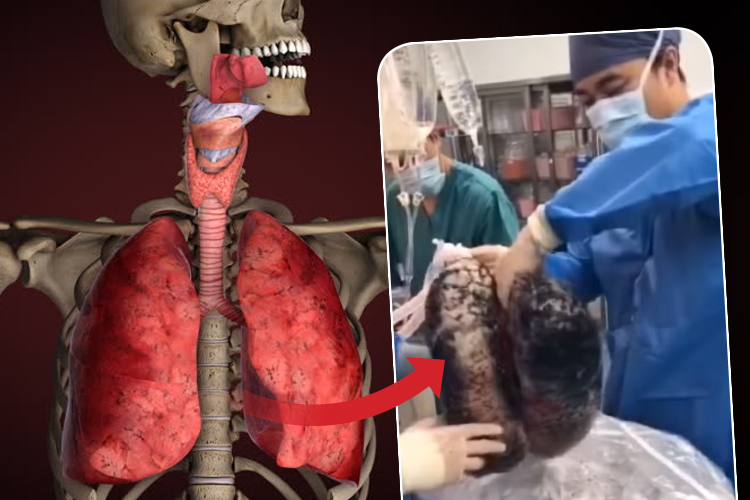

করোনার কামড়ে শক্ত হয়েছে ফুসফুস

সিগারেট এই ভাবে পুড়িয়ে দেয় ফুসফুসকে! দেখুন ভিডিয়ো

ভারতে প্রথম জোড়া ফুসফুস প্রতিস্থাপন